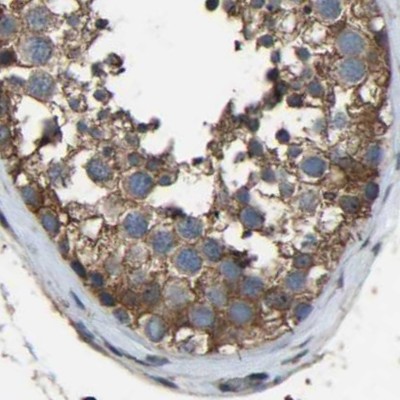

Immunohistochemical staining of human colon, kidney, lymph node and testis using Anti-FHIT antibody HPA018909 (A) shows similar protein distribution across tissues to independent antibody HPA018840 (B).